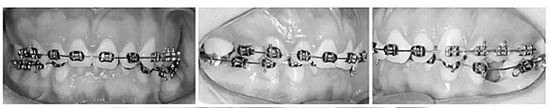

上下頜牙齒均粘貼0.022x0.028英寸的MBT托槽(3M / Abzil)并且使用0.014英寸的鎳鈦絲到0.020英寸的不銹鋼弓絲排齊、整平。

之后,在左上前磨牙之間植入種植釘,作為支抗,將右上部牙列向后移動(dòng)至I類關(guān)系(Figure 6a-c)。原本想采用微種植釘體來(lái)矯正傾斜的咬合面,然而,微種植釘動(dòng)度大,并且不能承受較大的負(fù)荷。取而代之的是,在左側(cè)上頜骨植入微鈦板作為支抗,用兩個(gè)懸臂(其用0.018x0.025英寸鈦-鉬絲制成)連接至鈦板上的兩個(gè)管并且系緊在弓絲上,以此壓低左側(cè)上頜后牙。此外,使用橫腭桿來(lái)避免左側(cè)后牙的頰傾(Figure 6d,e)。

在下頜從右下第二磨牙到尖牙以及從左下第二磨牙到第一磨牙使用片段弓,將0.018x0.025英寸的不銹鋼絲插入輔助管中并使用,直到下牙弓整平為止。在此之后,使用連續(xù)的弓絲來(lái)完成排齊整平。矯正上頜牙合平面后,在左側(cè)從微鈦板到下牙弓,使用頜間牽引伸長(zhǎng)左下后牙。